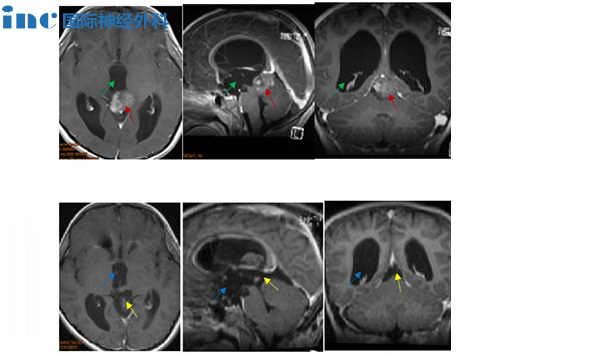

CASE 5:8岁男孩-松果体肿瘤

病史摘要:8岁男童出现头痛、眼球运动障碍等症状,经磁共振检查结果为“松果体区占位合并幕上梗阻性脑积水”。脑脊液分流加辅助放化疗半年后,早期症状并无好转。巴教授顺利全切。

手术过程:术中,患者俯卧位,后正中头皮切口,经幕上、幕下联合入路,肿瘤得以全切除,且尽力减少了组织的损伤,对预防后期肿瘤的复发起到了较大作用。

术后情况:术后一天患者清醒,术后ICU观察两天,术后一般情况好,无明显并发症,顺利出院。患儿的各种症状全都消失,恢复了正常机体功能,近期复查时肿瘤也并无增长。